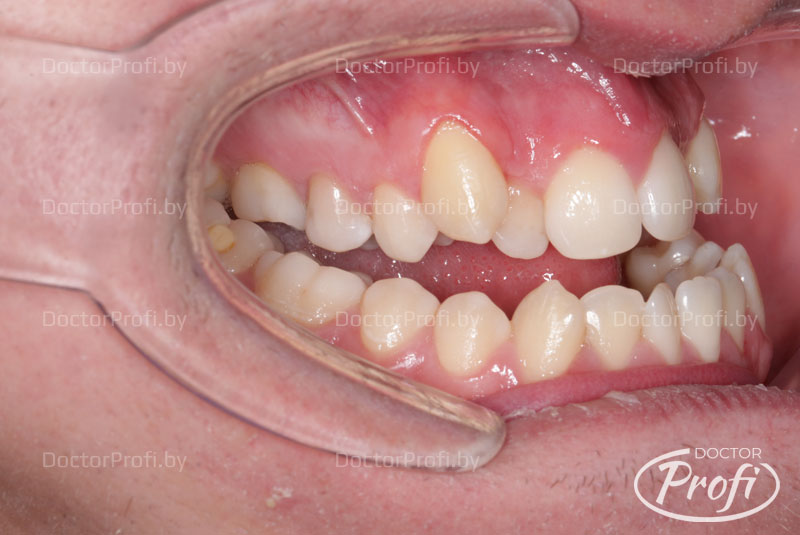

До